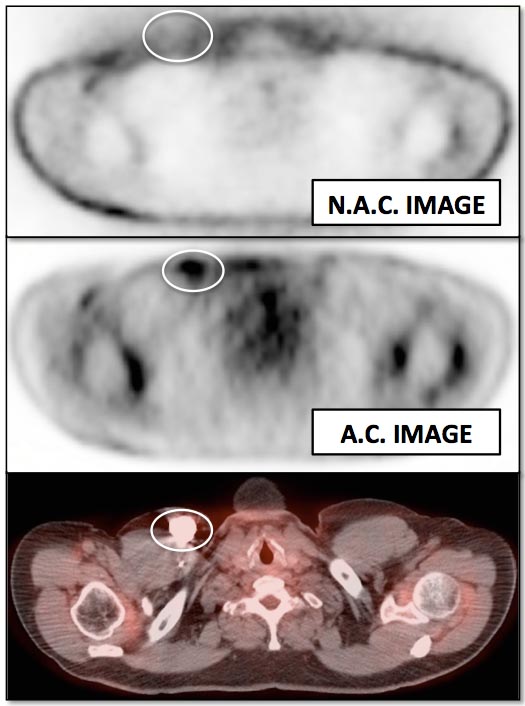

Attenuation Correction (AC) Artifacts:

On occasion (typically in older PET/CT machines), attenuation correction of PET images can result in falsely elevated metabolic activity in regions of high CT density (e.g. metallic devices, oral contrast, calcification).  In such cases, these areas must be reviewed on the NAC (non-attenuation correction) images. If these regions are not also hypermetabolic on the NAC images, then their apparent increased FDG-uptake on the AC images is artifactual (addressed in detail, here).